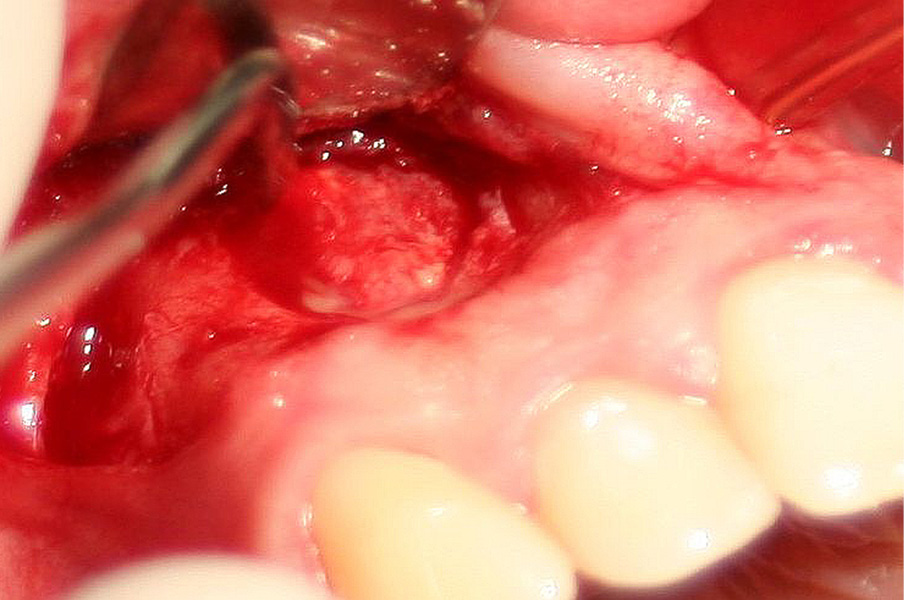

Streszczenie: Zastosowanie mikroskopu zabiegowego, mikroinstrumentów, narzędzi ultradźwiękowych i materiałów zaawansowanych biotechnologicznie zrewolucjonizowało tradycyjne techniki chirurgii endodontycznej. Przypadki endodontyczno-chirurgiczne klasy A, B i C predysponują do leczenia zachowawczego lub mikrochirurgicznego i w większości przypadków kończą się powodzeniem, w odróżnieniu od klas: D, E i F. Właściwe i skuteczne ich leczenie wymaga endodontycznych technik mikrochirurgicznych oraz sterowanej regeneracji tkanek.

Summary: Microscope, microsurgical instruments, ultrasonic instruments and advanced biotechnological materials has revolutionized traditional techniques in endodontic surgery. Class A, B and C of the clinical classification of endodontic-microsurgical cases predispose to conservative or microsurgery treatment and in most cases are successful. Cases D, E and F class are more difficult. Proper and effective treatment requires endodontic microsurgical techniques and guided tissue regeneration.

Mikrochirurgia endodontyczna to dział stomatologii wywodzący się z chirurgii endodontycznej (endodoncja chirurgiczna). Głównym jego celem jest diagnozowanie i leczenie zmian pochodzenia [...]